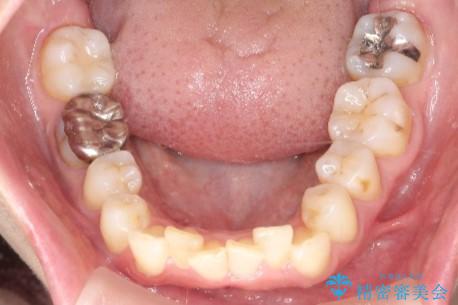

【インビザライン】前歯の凸凹を治したい

- 前歯の凸凹を主訴に来院されました。

臼歯部の遠心移動を行いながらスペースを作り、インビザラインにて前歯をきれいに並べることができました。

今回の治療計画では臼歯部の遠心移動とIPRを行っています。